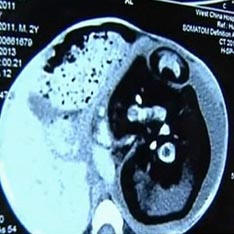

Хирурзите откриха нероденото му в стомаха на двегодишно дете Сиамски близнак. С необичаен случай в практиката си изправени пред лекари от Китай. След прегледа на лекарите двугодишно момче с огромен корем от село Хуаши, оказа се, че в него е бил неговият нероден брат близнак. Решено е да се подложи на спешна операция, тъй като стомахът е подут невероятни размери, вътрешните органи започнаха да се свиват и на бебето стана трудно да диша, пише Daily Mail. Оказа се, че брат, което беше вътре в него през цялото това време, не беше много по-малък от самото момче. Тялото му беше недоразвито, но гръбначният стълб, крайниците и пръстите на ръцете и краката са напълно оформени. Този случаят, обясниха лекарите, е една от разновидностите на сиамските близнаците. Те се раждат, когато оплодена яйцеклетка не се споделя напълно. Но, както отбеляза неонатологът от детската стая Болница в Кливланд д-р Джонатан Фанароф, в случая на “бременно” бебе, яйцето не сподели.

В цялата история на медицината има стотици случаи, когато един от ембрионите близнаци се „поглъща“ от брат му и продължава развитие в него. Това явление винаги се появява рано. етапи на бременността и обикновено и двата плода умират в утробата майка. Случва се обаче раждането да е успешно и да се залови трапният ембрион продължава да живее като паразит, свързан с него голям брат вид пъпна връв. В крайна сметка той става толкова голям, че започва да навреди на себе си до собственика. В медицината тази аномалия се нарича плод във фетус (ембрион в ембриона). Между другото, беше записан същия случай преди няколко години в Индия. Коремът на 36-годишната Санджу Бхагат беше издуха дотолкова, че той приличаше на жена, която се канеше ще роди. Хирурзите бяха сигурни, че той има огромен тумор, който натиска върху диафрагмата. Но каква беше тяхната изненада, когато излезе от него те извадиха утробата на мутираното тяло на брат му близнак.